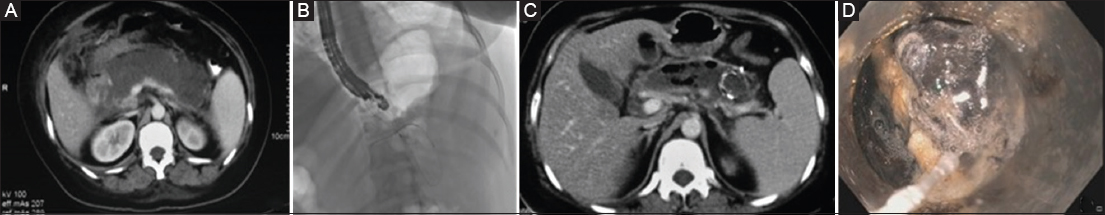

Figure 3 (A) Computed tomography at day 19: an ill-defined pancreatic necrosis. (B) LAMS being deployed. (C) Computed tomography after metal stent placement. (D) Cap-assisted endoscopic necrosectomy LAMS, lumen-apposing metal stents